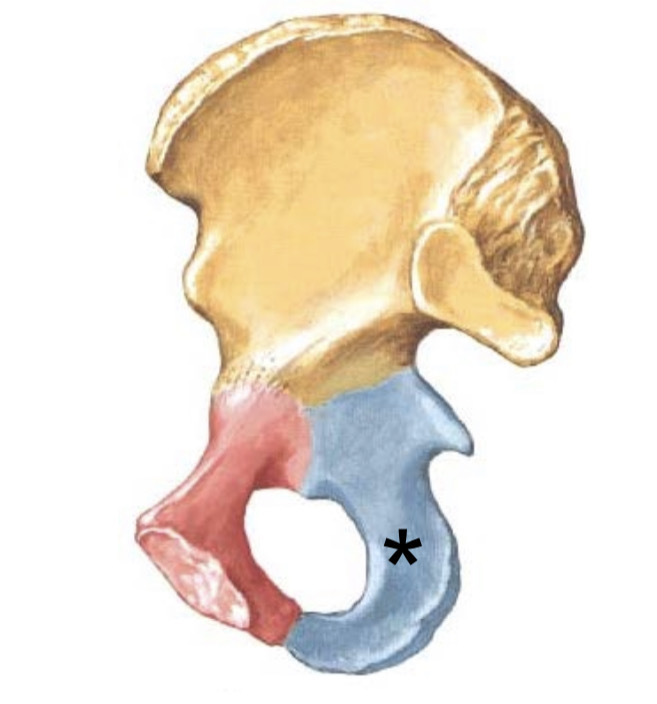

Een voetballer scheurt zijn rechter ligamentum cruciatum anterior.

Welke beweging is nog mogelijk?